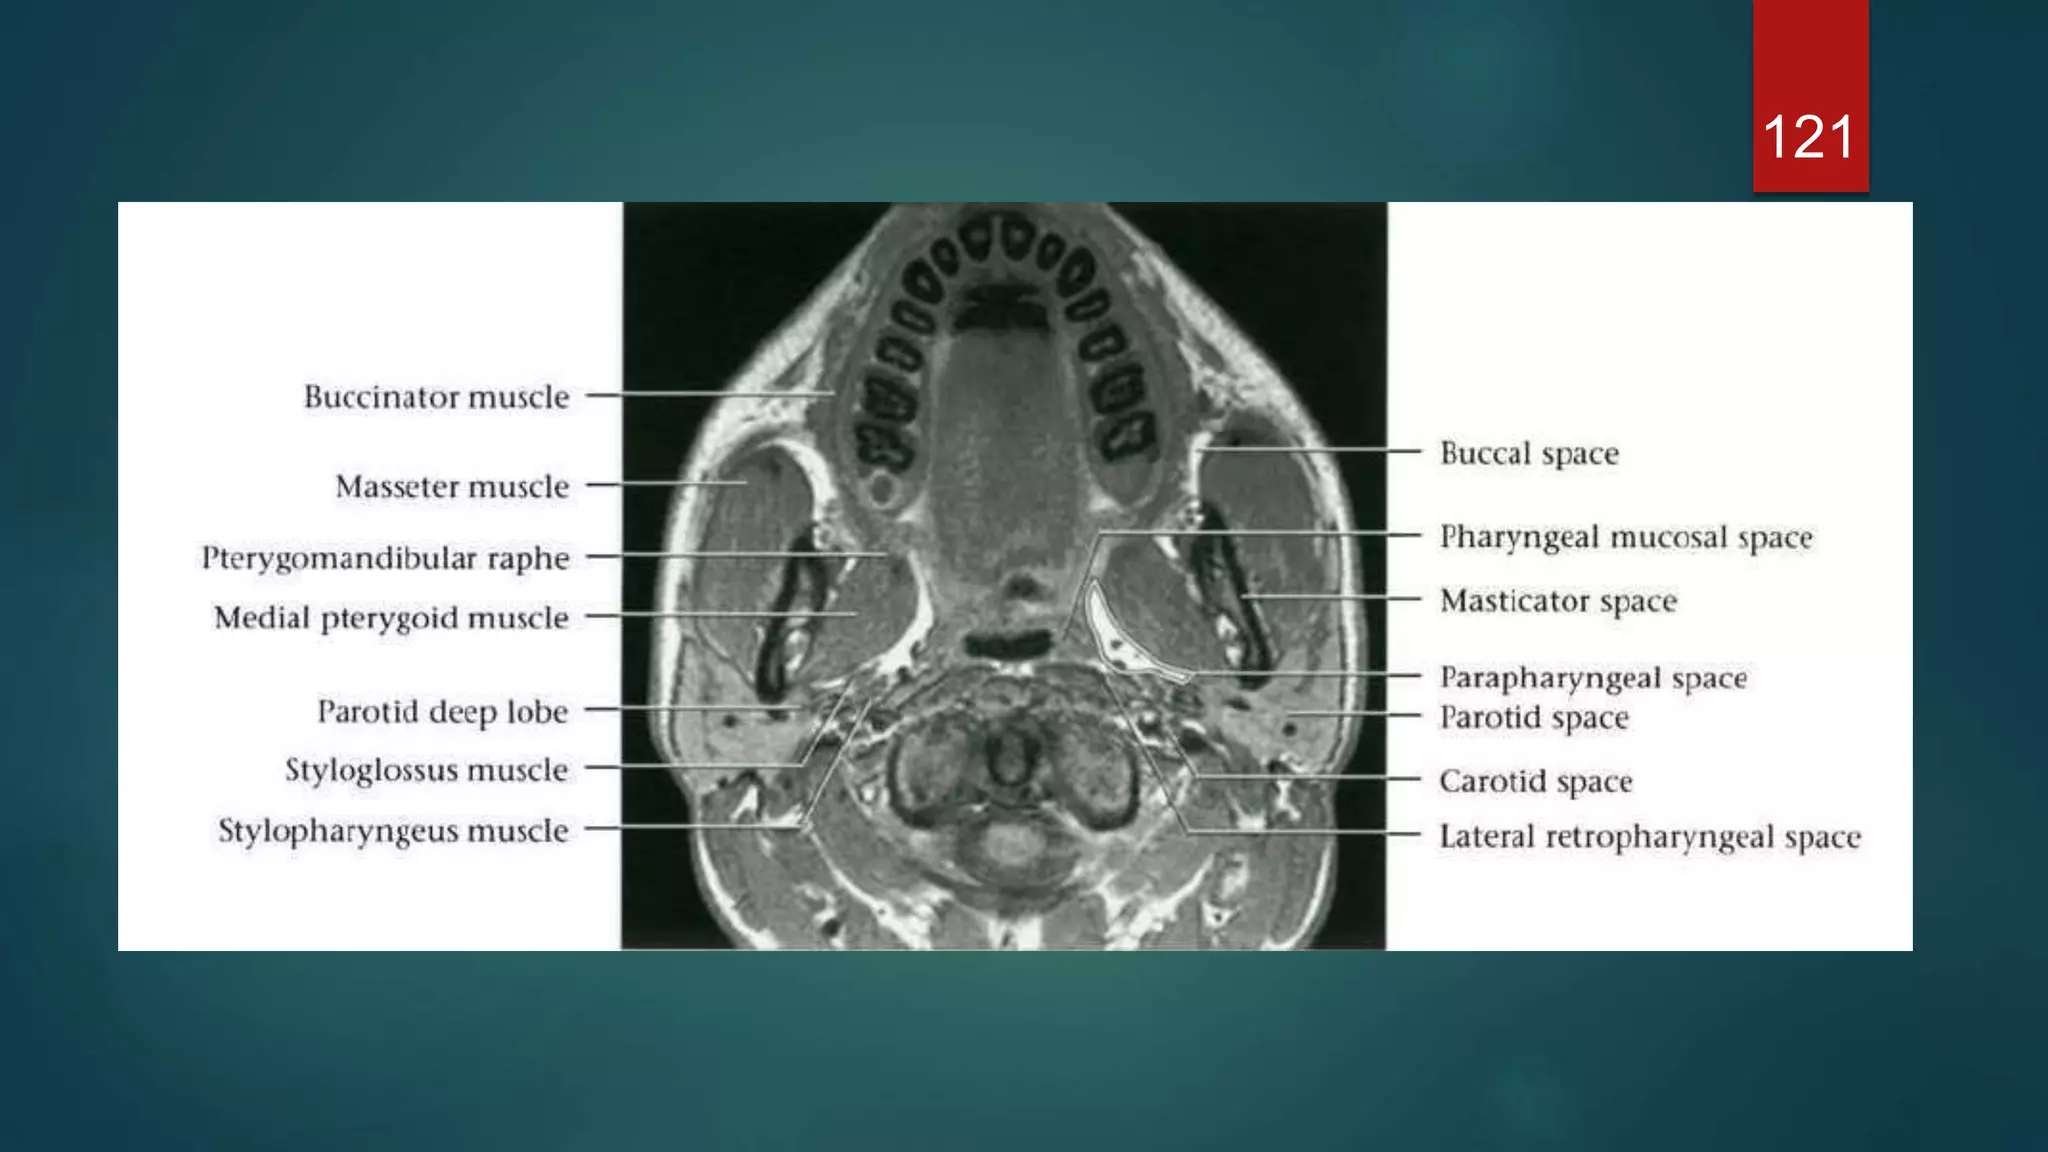

119

120

121